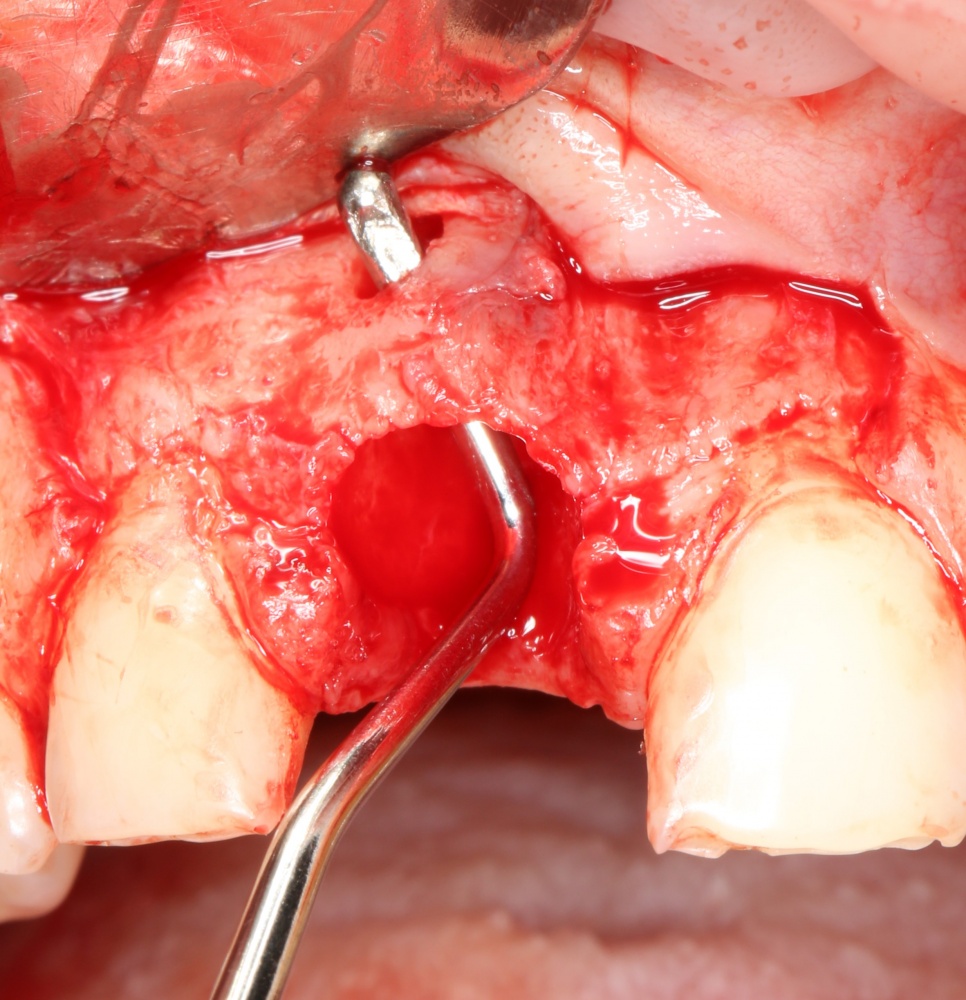

После удаления зуба и сопутствующей гранулемы, остается большая по размеру лунка с тонкой и поврежденной воспалительным процессом вестибулярной стенкой:

Первым делом, необходимо определиться с подготовкой лунки под имплантат. Проверить правильность позиционирования лунки можно с помощью аналогов имплантов, входящих в комплект XiVE Dentsply Implants:

Напомню, что при правильном позиционировании импланта в области фронтальных зубов, он прилегает к небной стенке лунки, а его ось выходит на небную поверхность будущей коронки. В крайнем случае, на режущий край.

Имплантат по объему всегда меньше, чем сам зуб:

Поэтому у нас возникает вопрос заполнения «пустого» пространства между вестибулярной стенкой лунки и поверхностью импланта. И, как ни странно, с Bio-Oss Collagen это удобнее сделать до установки имплантата.

Графт адаптируется (с помощью скальпеля), устанавливается в нужное положение. Для этого, опять же, очень удобно использовать аналоги имплантов из имплантологического набора (в крайнем случае, остеотомы или пины параллельности):